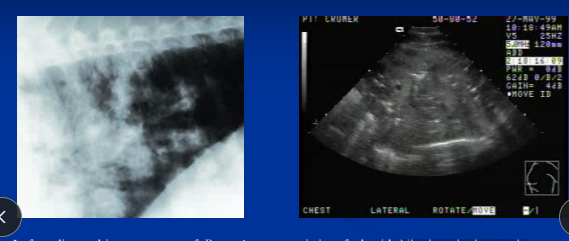

Dt: murmurs, prerenal azotemia, high hepatic enzymes, high CVP, echo w/ chamber enlargement + poor function, rad w/ cardiomegaly + pulmonary edema

Pericarditis in horses

Et: Inflam of pericardium, Actinobacillus, Strep zoo, influenza, EVA, AHS

Fibrinous or Effusive

Cs: fever, depression, exercise intolerance, weakness, tachycardia, muffled heart sounds, weak pulses, circulatory collapse

Dt: Echo (effusion), Pericardial tap, ECG w/ Low QRS amp

Tx: Pericardial drainage + lavage, Antibiotics, Corticosteroids

Prognosis poor